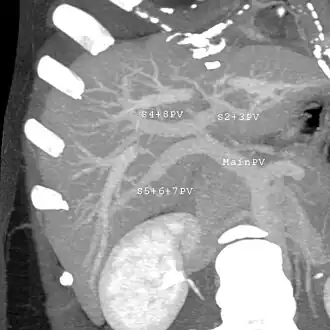

Couinaud classification system

In the widely used Couinaud system, the functional lobes are further divided into a total of eight subsegments based on a transverse plane through the bifurcation of the main portal vein.[30] The caudate lobe is a separate structure that receives blood flow from both the right- and left-sided vascular branches.[31][32] The Couinaud classification divides the liver into eight functionally independent liver segments. Each segment has its own vascular inflow, outflow and biliary drainage. In the centre of each segment are branches of the portal vein, hepatic artery, and bile duct. In the periphery of each segment is vascular outflow through the hepatic veins.[33] The classification system uses the vascular supply in the liver to separate the functional units (numbered I to VIII) with unit 1, the caudate lobe, receiving its supply from both the right and the left branches of the portal vein. It contains one or more hepatic veins which drain directly into the inferior vena cava.[30] The remainder of the units (II to VIII) are numbered in a clockwise fashion:[33]

With the recent advances of noninvasive imaging, living liver donors usually have to undergo imaging examinations for liver anatomy to decide if the anatomy is feasible for donation. The evaluation is usually performed by multidetector row computed tomography (MDCT) and magnetic resonance imaging (MRI). MDCT is good in vascular anatomy and volumetry. MRI is used for biliary tree anatomy. Donors with very unusual vascular anatomy, which makes them unsuitable for donation, could be screened out to avoid unnecessary operations.